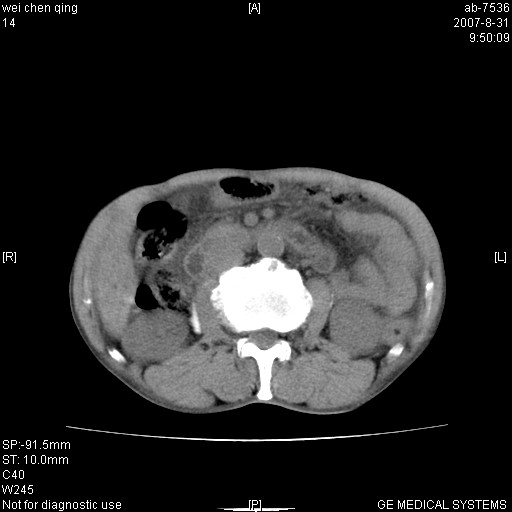

以下是引用zjzjr在2007-8-31 14:38:00的发言:[br]胰头癌伴肝内胆管扩张可能性大。

以下是引用zyyzzy在2007-8-31 14:34:00的发言:[br]该病人肝内胆管扩张,胆囊及胆总管未见明显扩张。在倒数第9层图像上可看到左右肝管结合部(肝总管)有软组织影,此处应薄层扫描。考虑肝总管占位(ca)、腹水。[br]